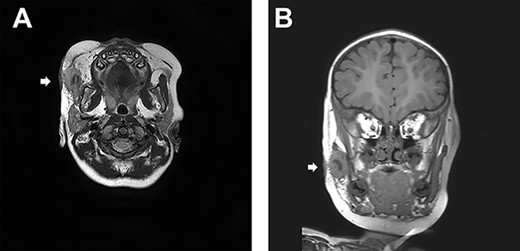

At the age of one and a half, his right cheek was swollen with a slight fever (Fig. 2). magnetic resonance imaging (MRI) presented a cystic lesion beneath the superficial musculo-aponeurotic system (Fig. 3). Although antibiotic was administered, it ruptured to the skin during the preparation period for the operation. Staphylococcus aureus was detected in the pus.

(A) A transverse sT2W mDixon MRI image. A cystic lesion beneath the superficial musculo-aponeurotic system is identified. (B) A coronal section of MRI.